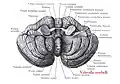

В последние годы жизни в Галле Рейль заинтересовался нейроанатомией, особенно после лекции, которую летом 1805 прочитал френолог Ф. И. Галль. Иоганн Христиан Рейль начал изучать мозжечок, публикуя большинство работ в 1807-1809. Он известен в анатомии мозга множественными эпонимами после изучения его строения и химического состава:

- Дугообразный пучок (пучок Рейля, лат. fasciculus arcuatus) соединяет клетки язычка, клетки ядра шатра с латеральным, медиальным и верхним преддверными ядрами;

- Рейля циркулярная борозда (синоним: круговая борозда островка, лат. sulcus circularis insulae);[15]

- Рейля углубление (синоним: долинка мозжечка, лат. vallecula cerebelli);

- Рейля треугольник (синоним: треугольник петли, лат. trigonum lemnisci);

- Рейля связка (синоним: медиальная петля, лат. lemniscus medialis);

- Рейля петля (синоним: петля мозговой ножки, лат. ansa peduncularis);

- Рейля островок (синоним: островковая доля, лат. lobus insularis);

- Рейля волокна (синоним: латеральные полоски мозолистого тела, лат. striae longitudinales laterales);

- Он первым описал структуру, известную как покрышка (лат. tapetum) мозолистого тела;

Рейля островок (здесь и далее структура отмечена красным)

Рейля островок (здесь и далее структура отмечена красным) Рейля петля

Рейля петля Треугольник Рейля

Треугольник Рейля Углубление Рейля

Углубление Рейля

Из других эпонимов хорошо известен палец Рейля (лат. Digitus mortuus)[16], линии Бо[17]-Рейля на ногтях (описаны Рейлем за 50 лет до Д. О. С. Бо, в 1796)[18] и канатик Рейля.

Рейля канатик

Рейля канатик